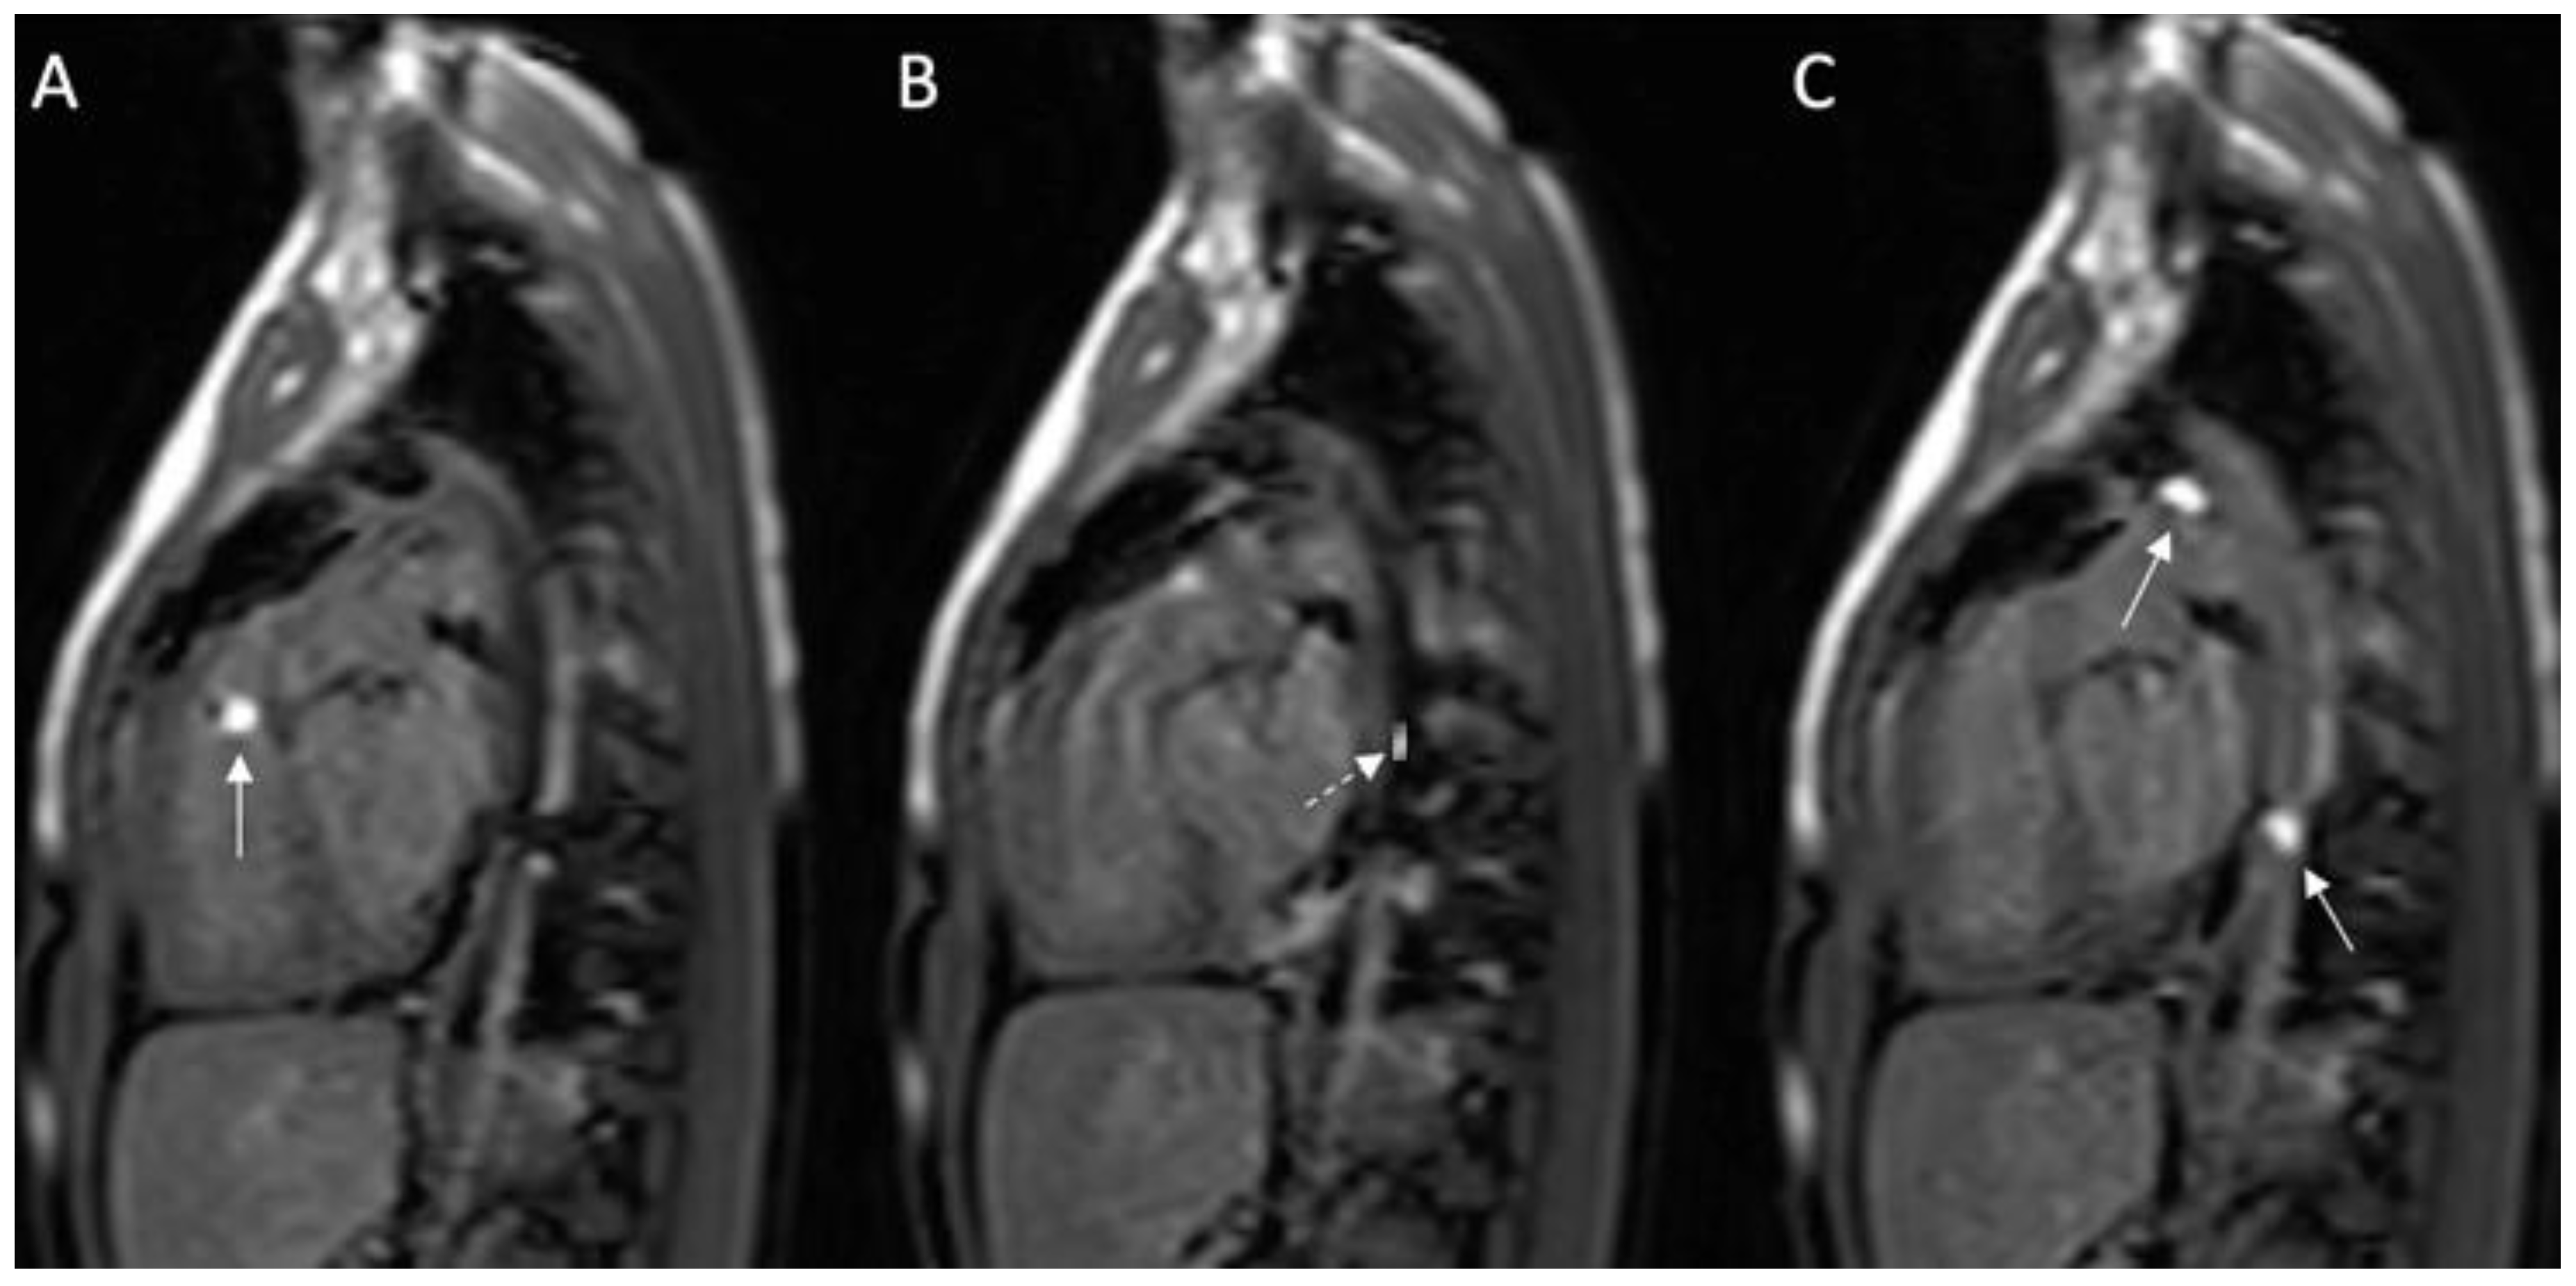

- Reddy, S.R.V.; Arar, Y.; Zahr, R.A.; Gooty, V.; Hernandez, J.; Potersnak, A.; Douglas, P.; Blair, Z.; Greer, J.S.; Roujol, S.; et al. Invasive cardiovascular magnetic resonance (iCMR) for diagnostic right and left heart catheterization using an MR-conditional guidewire and passive visualization in congenital heart disease. J. Cardiovasc. Magn. Reson. 2020, 22, 20. [Google Scholar] [CrossRef] [PubMed]

- Ratnayaka, K.; Kanter, J.P.; Faranesh, A.Z.; Grant, E.K.; Olivieri, L.J.; Cross, R.R.; Cronin, I.F.; Hamann, K.S.; Campbell-Washburn, A.E.; O’Brien, K.J.; et al. Radiation-free CMR diagnostic heart catheterization in children. J. Cardiovasc. Magn. Reson. 2017, 19, 1–10. [Google Scholar] [CrossRef] [PubMed]